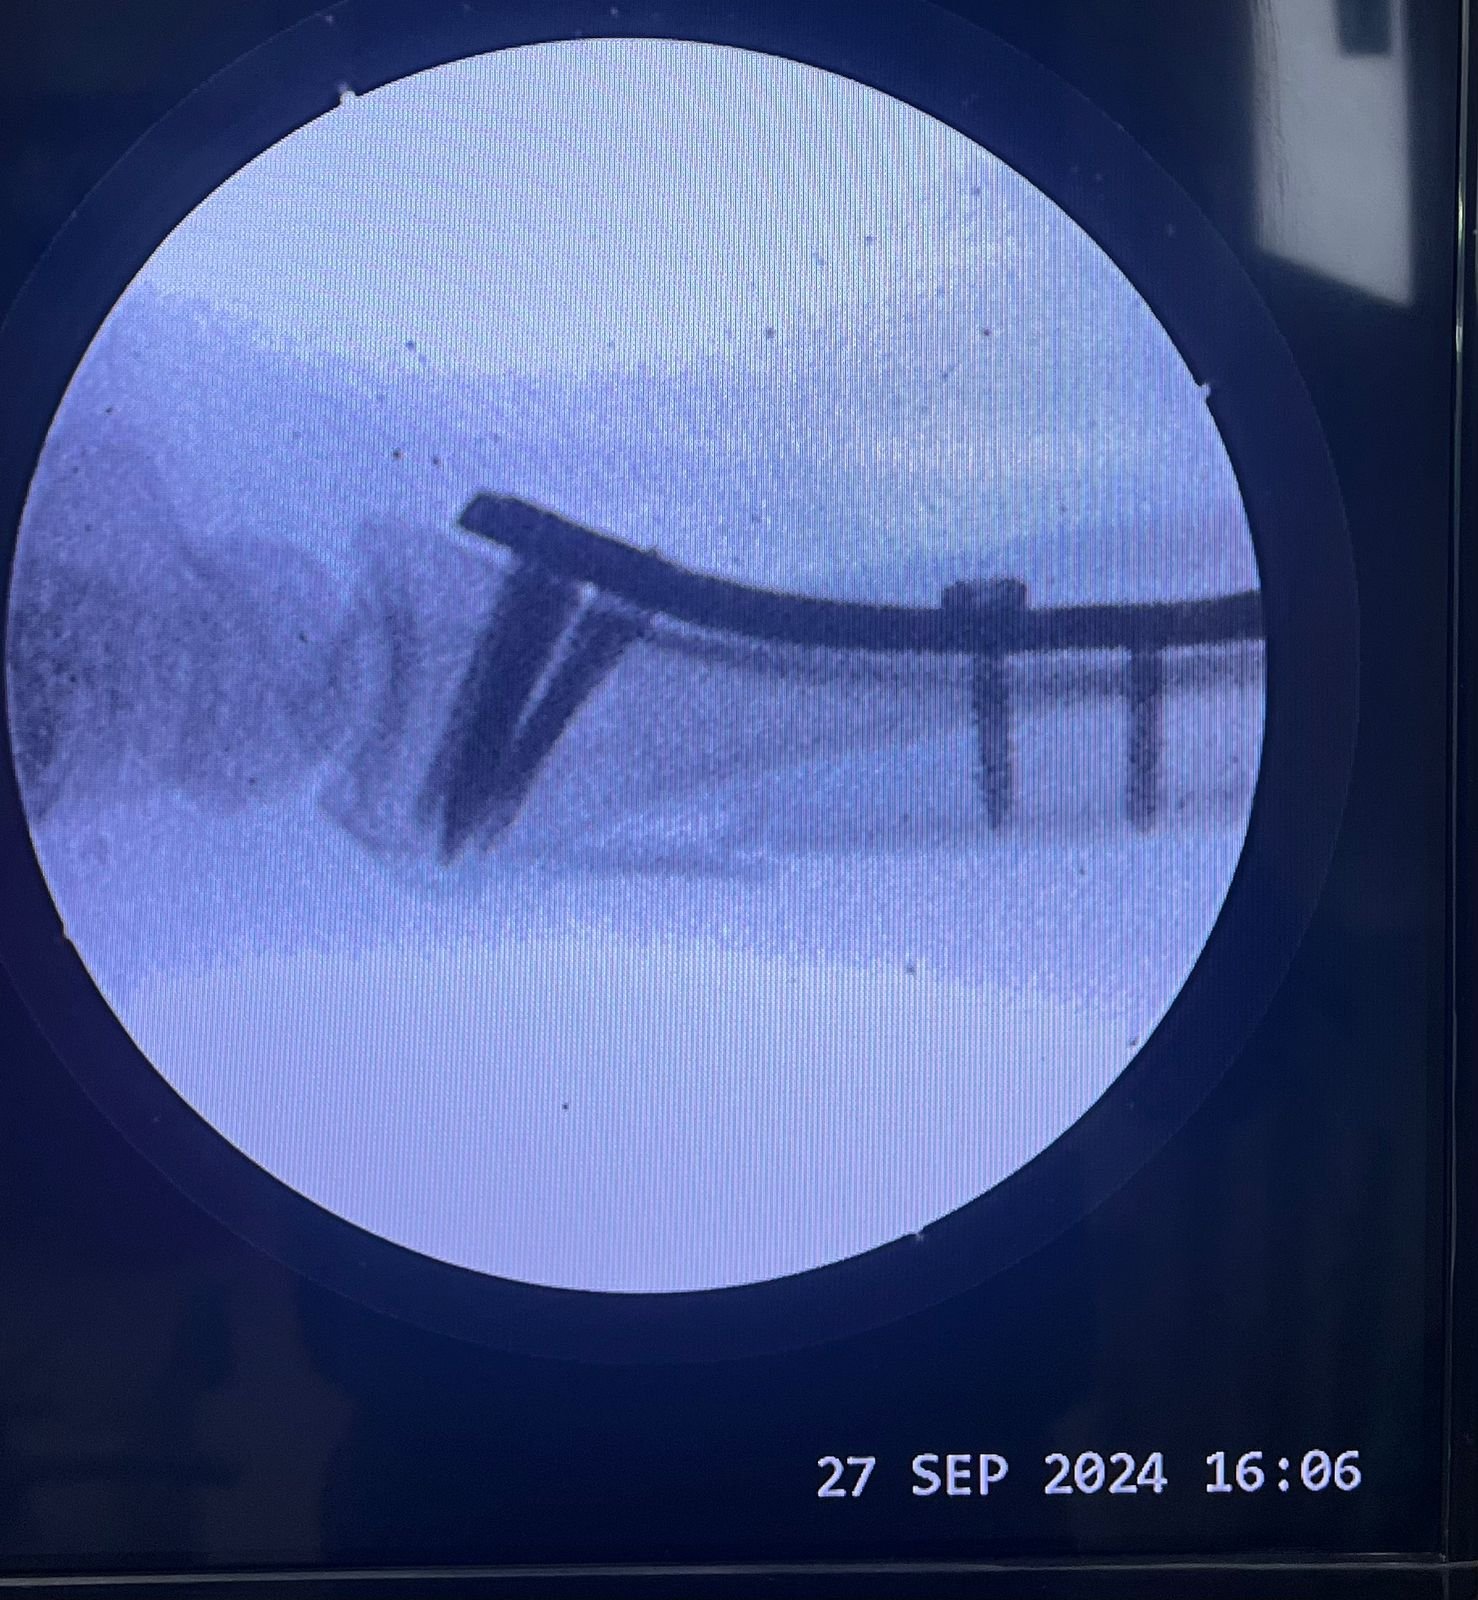

Non union with Broken DCS implant & revision

correction surgery